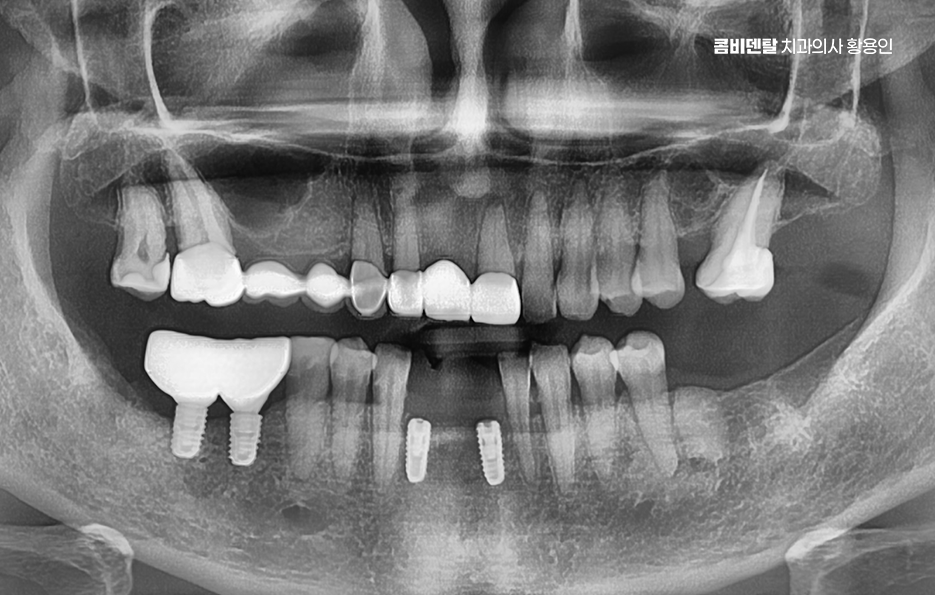

임플란트 치료의 주된 원리는 '골유착'에 있는데 이 단어가 조금 생소할 수 있지만 쉽게 말하면 임플란트의 인공치근, 자연치의 뿌리 역할을 대신하는 인공치근은 티타늄 재질로 구성되어 있고 잇몸뼈 안에 심으며 그 뼈가 이 인공치근을 자기 뼈처럼 감싸서 단단하게 붙는 현상을 말하는 거예요

티타늄은 인체에 생물학적으로 안정적인 금속이라서 뼈가 이물질로 인식하지 않고 잘 달라붙는 성질이 있는 것으로 치조골 안에 이 티타늄으로 구성된 인공치근이 수개월 동안 안정적으로 뼈와 결합되는 과정을 거치게 되면서 자연치아에 버금가는 저작력을 갖추게 되는 것이 주된 치료 원리라고 할 수 있었어요

임플란트의 장점 이 골유착이 완성된 이후에는 그 위에 기둥을 세우고, 마지막으로 보철물을 씌우게 되는데 이렇게 되면 겉에서 보기엔 자연치아와 거의 차이가 없으며 심지어 기능적으로도 자연치아와 유사한 수준의 저작력이 가능해지며 다시 말해 뿌리부터 머리까지 인공치아를 만드는 건데 ‘뼈에 심는’ 것이기 때문에 더 안정적이고 오래 쓸 수 있는 치료인 거예요.